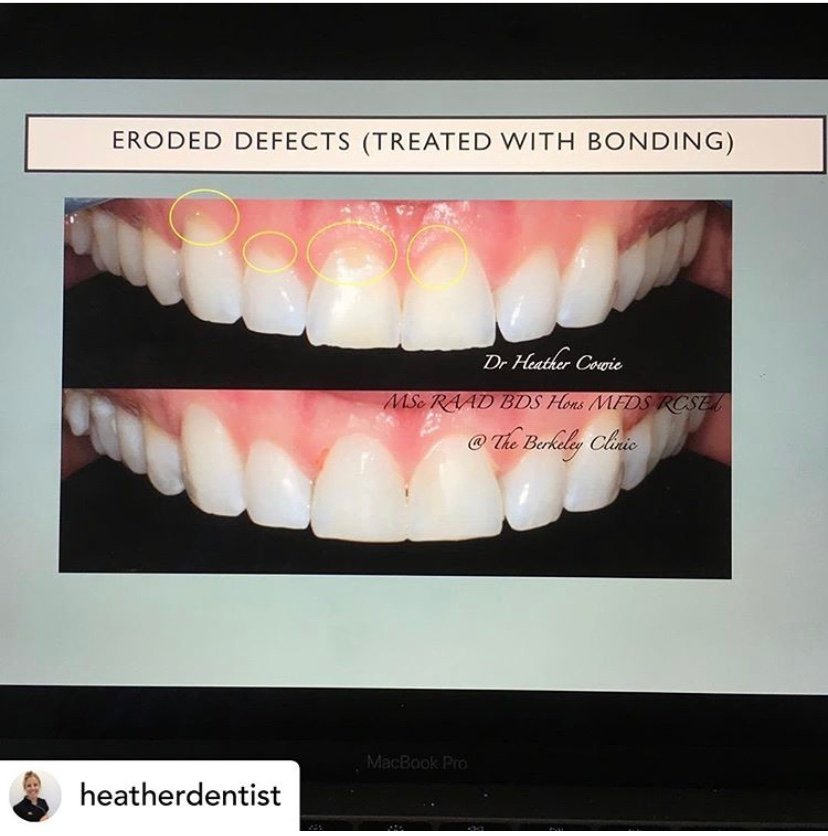

The Berkeley Clinic

Berkeley Clinic provides all levels of Cosmetic and Restorative Dentistry in Glasgow, including Dental Implants Invisalign Clear Braces and Teeth Whitening.